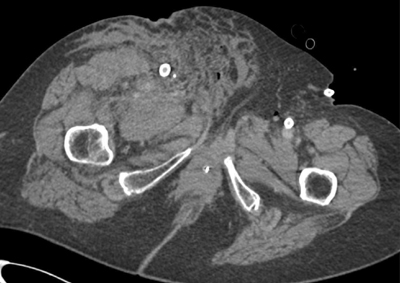

Figure 2

An axial CT showing extensive inguinal blood at the level of the right superficial femoral artery.